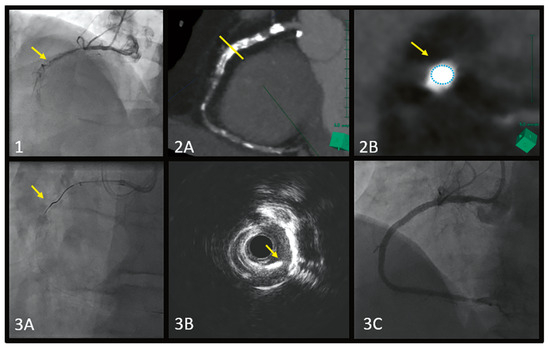

Full Moon Coronary Calcium Seen on Cardiac Tomography, Can It Change PCI Decision-Making and Procedure?

by Youssef S Abdelwahed, Carsten Skurk, Patrick T. Siegrist, Ulf Landmesser and Gerald S. Werner

We report the case of a 57-year-old mal complaining of recurrent chest pain admitted electively for a recanalisation attempt to a known chronically totally occluded right coronary artery (RCA). [...] Full article